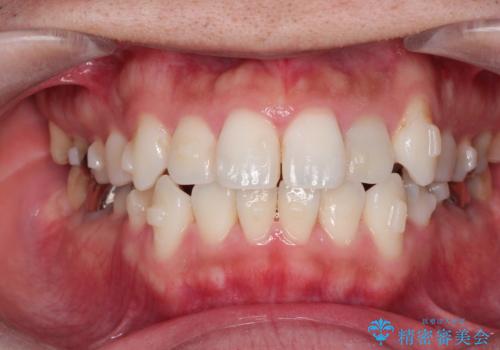

インビザラインで目立たない矯正 ガタガタの歯並びをきれいな歯並びへ

- 全体的なガタガタが気になるとのことで来院されました。

歯と歯のあいだをわずかに削りスペースを作り、ガタガタを改善する計画としました。

装着時間をしっかり守っていただけたのでスムーズに治療をすすめることができました。